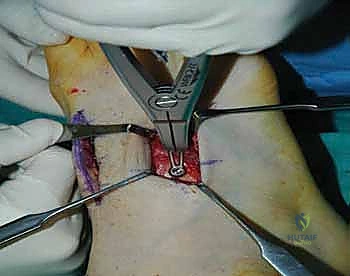

2. الشق الجراحي والوصول للمفاصل

يتم عمل شق جراحي واحد أو شقين (أحدهما في الجزء العلوي الداخلي والآخر في الجزء الخارجي) للوصول إلى مفاصل منتصف القدم دون الإضرار بالأوتار الحيوية والأعصاب والأوعية الدموية. يتم استخدام تقنيات الجراحة الدقيقة (Microsurgery) للحفاظ على الأنسجة المحيطة السليمة.

3. إزالة الغضاريف التالفة (Joint Preparation)

هذه هي الخطوة الأهم. يقوم الجراح بكحت وإزالة جميع الغضاريف المريضة والتالفة من بين العظام المراد دمجها. يجب الوصول إلى العظم الإسفنجي الصحي (Cancellous bone) الذي ينزف دماً، لأن هذا الدم يحتوي على الخلايا الجذعية وعوامل النمو الضرورية لعملية الالتحام (Fusion).